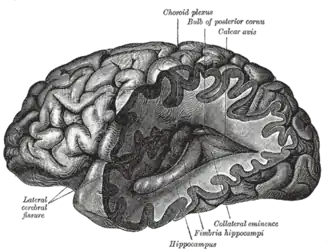

Nervous system

The nervous system is the system of neurons, or nerve cells that relay electrical signals through the brain and body. A nerve cell receives signals from other nerve cells through tree-branch-like extensions called dendrites and passes signals through a long extension called an axon (or nerve fiber). Synapses are places where one cell's axon passes information to another cell's dendrite by sending chemicals called neurotransmitters across a small gap called a synaptic cleft. Synapses occur in various locations, including ganglia (singular: ganglion), which are masses of nerve cell bodies. Preganglionic nerve cells in the sympathetic nervous system (all of which come from the lateral grey column), use the neurotransmitter acetylcholine, while postganglionic sympathetic nerve cells use norepinephrine.[1] Grey matter in the brain and spinal cord is any accumulation of cell bodies and neuropil (neuropil is tissue rich in nerve cell bodies and dendrites). White matter consists of nerve tracts (groups of axons) and commissures (tracts that cross the brain's midline).[2]